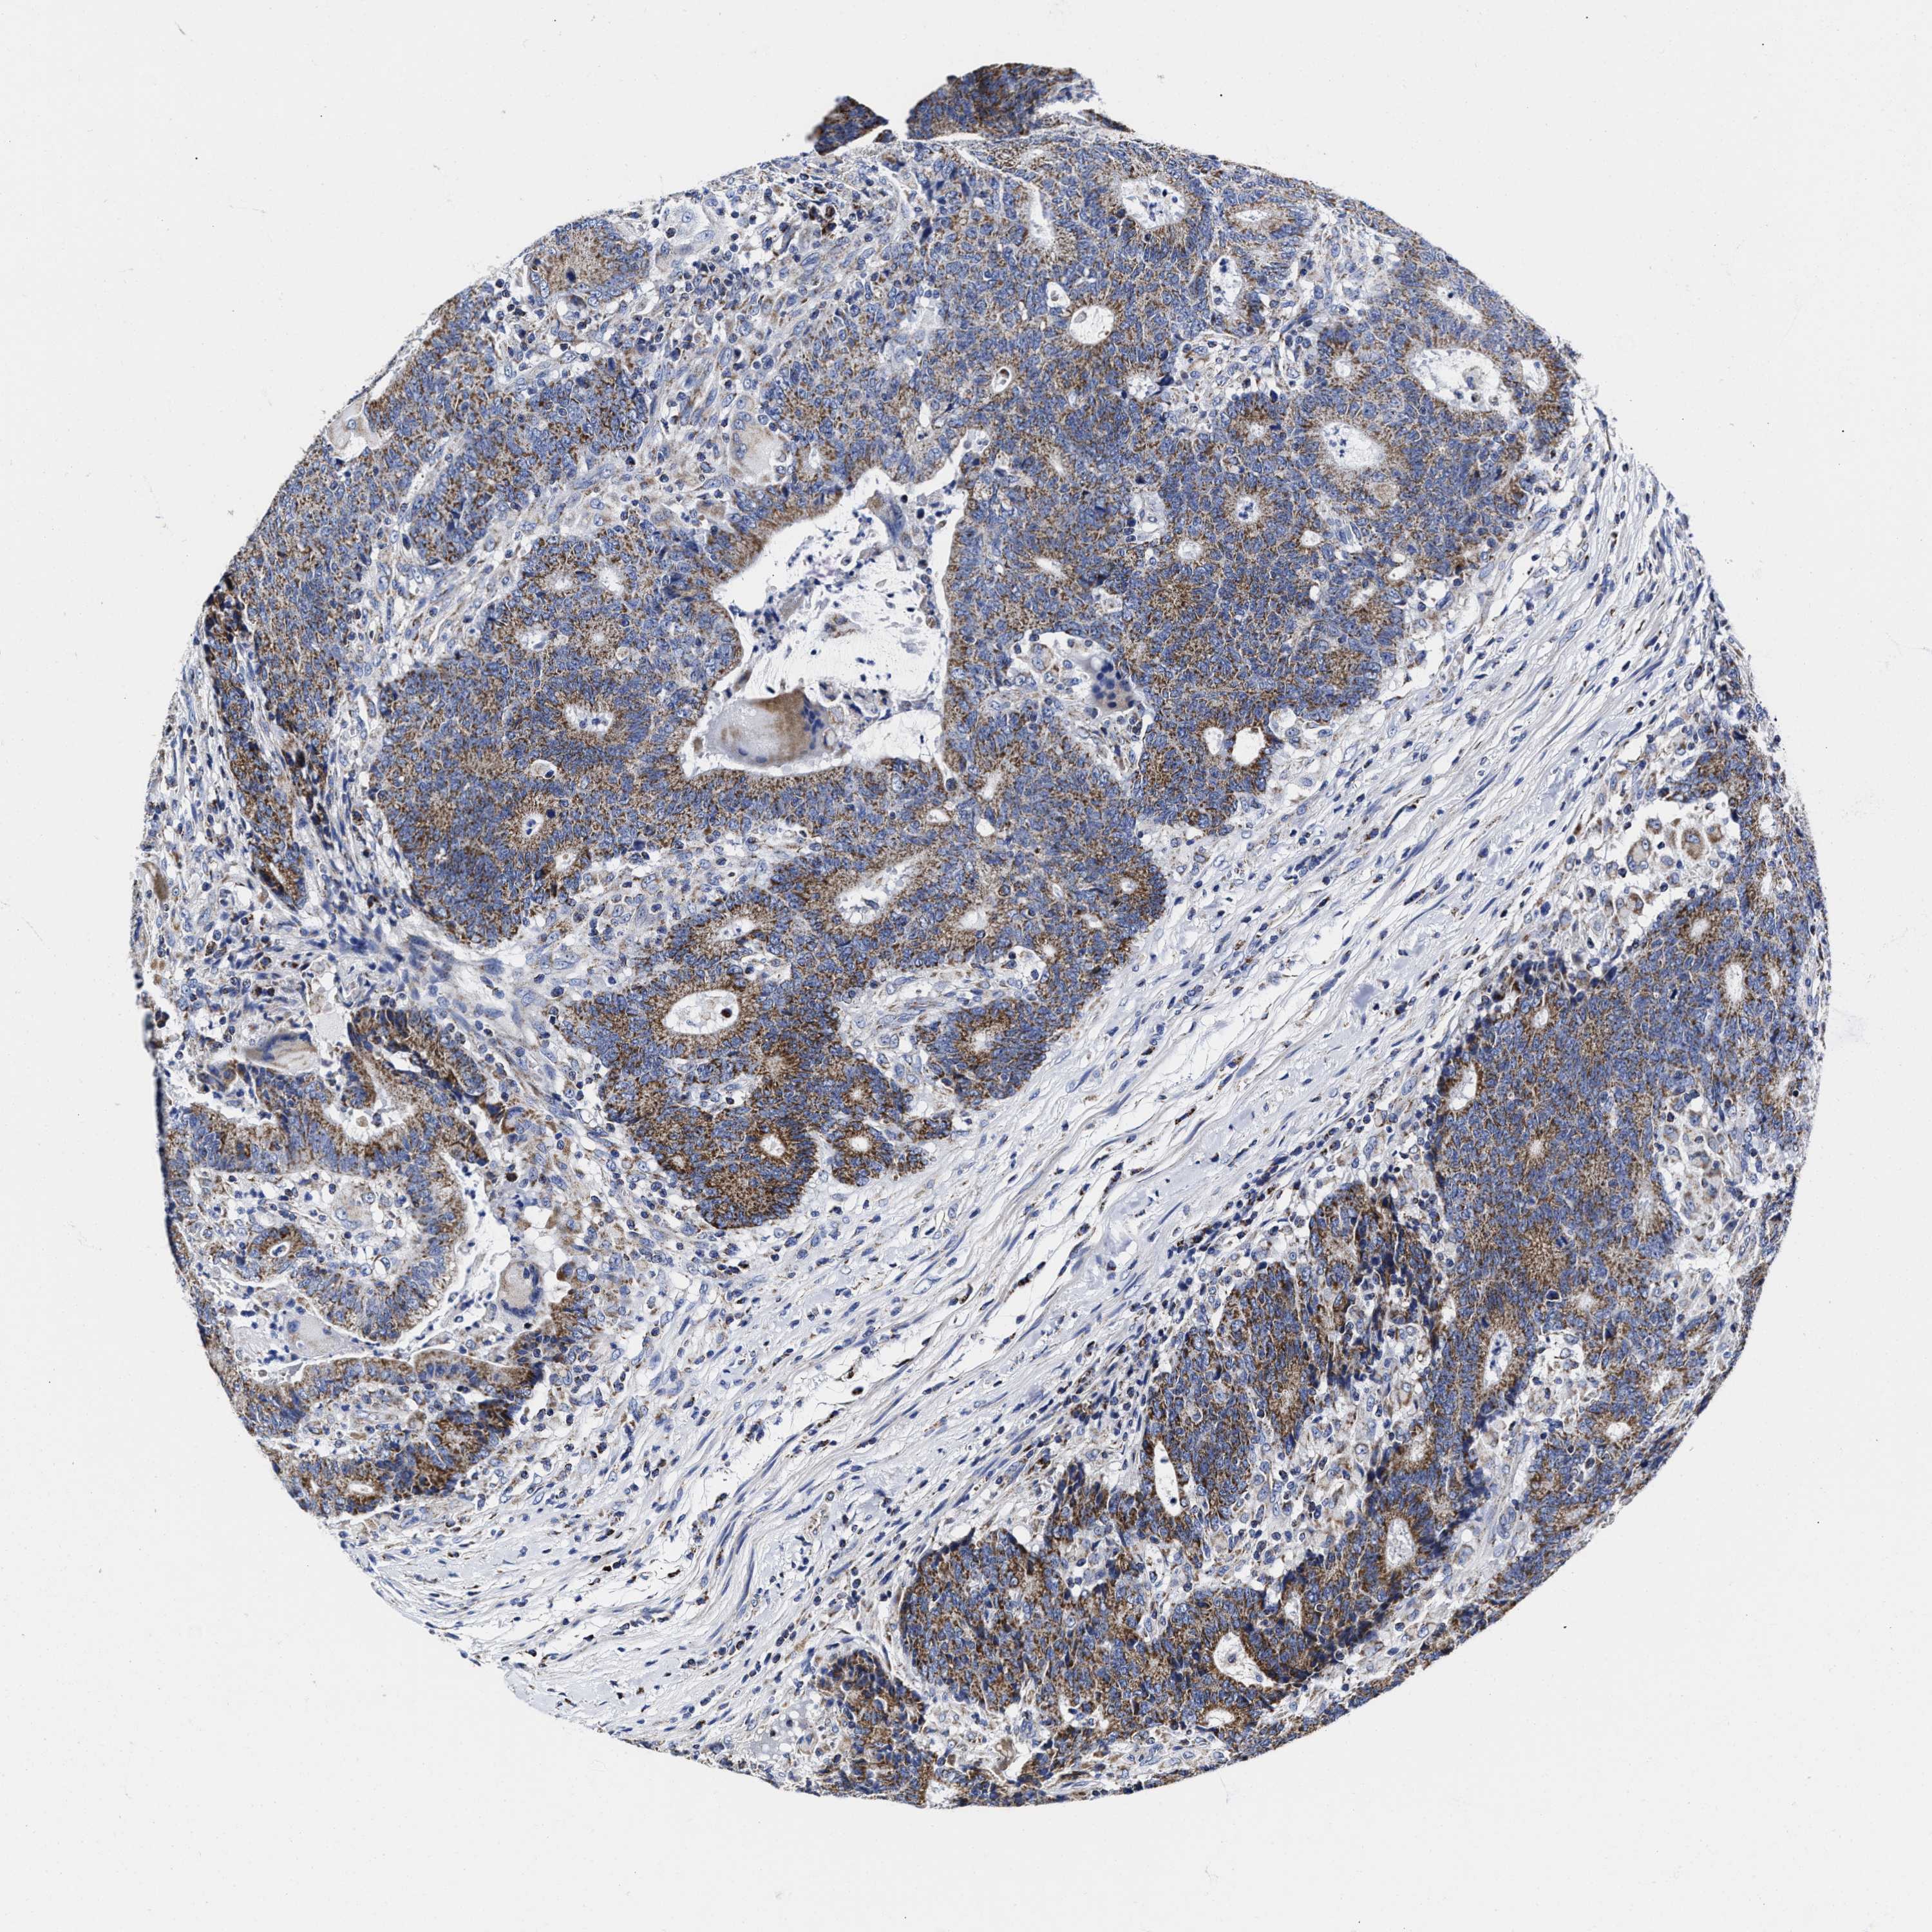

CANCER COLORECTAL CANCER Show tissue menu

Colorectal cancer

Human cancer

Colon adenocarcinoma